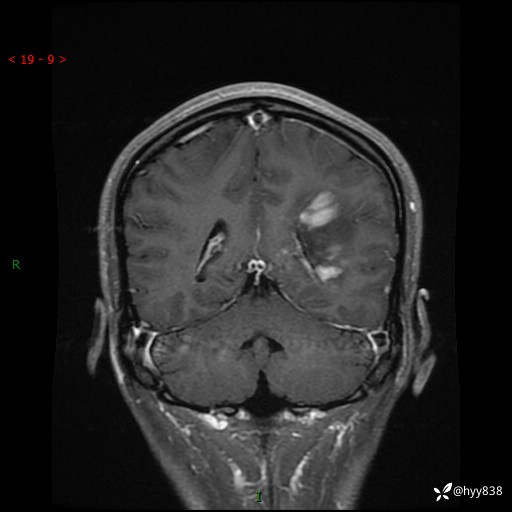

颅脑MRI平扫+增强